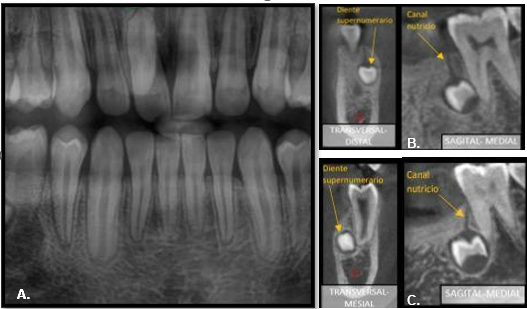

En la radiografía panorámica se observó la presencia de tres dientes supernumerarios incluidos.

La tomografía computarizada de haz cónico (TCHC) describió la ubicación de los dientes supernumerarios parapremolares en los cuadrantes tres y cuatro,

en formación coronaria parcialmente completa e inmediatos a los tercios medios radiculares de los dientes adyacentes (Figura 1).

Figura 1. Radiografía panorámica de mesiodens sobreproyectado en diente 1.1 (A), cortes tomográficos de parapremolar derecho (B) y parapremolar izquierdo (C).